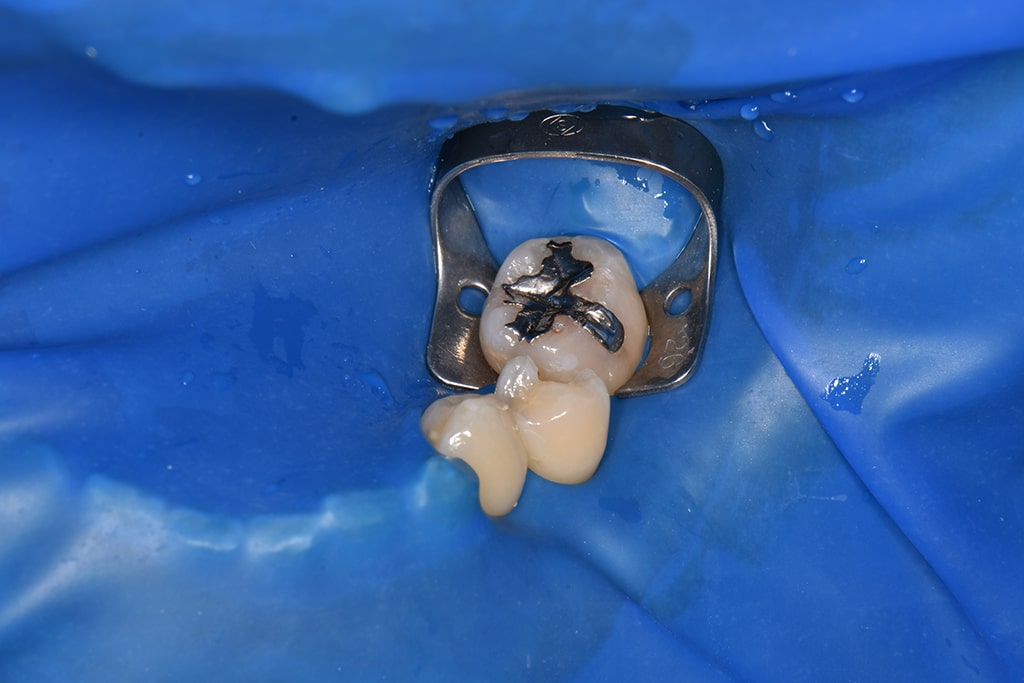

ラバーダム

治療する歯だけを露出して、唾液などが患部に侵入しないように保護する薄いゴム状のシートです。再感染予防のほか、薬剤などが口腔内に流れ込むことも防ぎます。ラバーダムの使用により、根管治療の成功率が格段に上がります。

ラバーダム防湿による無菌的処置

ラバーダムを使用する目的として、以下のような重要な役割が挙げられます。

- 無菌的処置(治療する歯に唾液などが

かかるのを防ぐ) - 治療時に術野を見えやすくする

- 治療時に使用する薬品が口の中に

流れるのを防ぐ - 器具が誤って口の中に入るのを防ぐ

精度の高い根管治療を行うには、無菌的環境のもとでの処置が不可欠です。

ラバーダム防湿とは、根管治療を行う際、治療する歯にラバーダムというゴムのシートを掛けることで術野に唾液等が入り込むのを防ぐことができます。

歯科先進国アメリカなど海外の根の治療の専門医は、このラバーダムを100%使用していますが、日本ではこのラバーダム防湿を行っていない医院が多く、それが国内の歯科医院における根管治療の成功率が低い理由として挙げられるほど、重要な役割をもつ医療器具です。